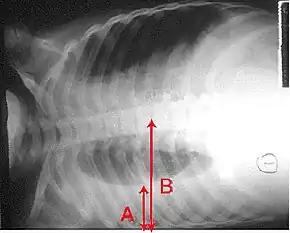

Anteroposterior chest X-ray of a pleural effusion. The A arrow shows fluid layering in the right pleural cavity. The B arrow shows the normal width of the lung in the cavity